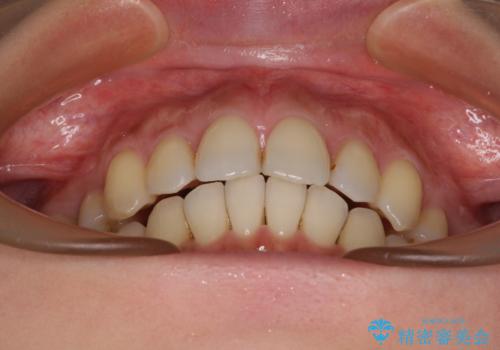

インビザラインにて抜歯矯正を行うと、高頻度で奥歯が咬み合わなくなります。

また、抜歯スペースに向けて奥歯が移動する際、必ず傾斜して移動するため、仕上がりの咬み合わせはワイヤー矯正と比べて明らかに劣ります。

抜歯スペースが閉じてからも咬みにくさ改善のためマウスピース矯正を継続するため、治療期間は長期化します。